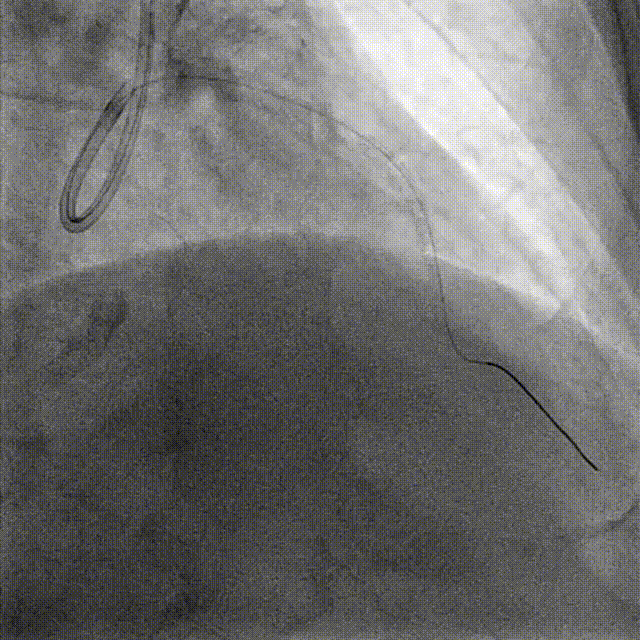

PCI-LAD TR, 7F EBU3.5

ROTA with 2.0mm burr

Angiography & Angioplasty NC 2.5*12mm